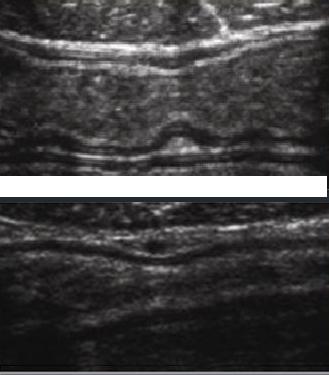

Image echographique

normale de l ' intestin :

Intestin grele : Image

echographique normale |

L'epaisseur de la paroi de

l'intestin normalement est en moyen a 3mm avec des

plies muqueuses et de peristaltisme marquee .

Au ileon la hauteur des plies

muquese est diminue et espace entre des plies

muqueuse sont augementes |

Jejunum : Important de

la presence de plissement de la muqueuse et en

connivence |